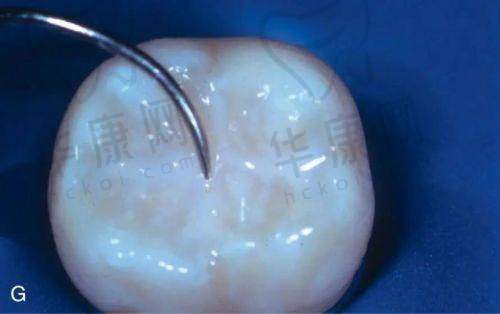

深圳善贝口腔儿童窝沟封闭150元起,这一实惠的价格为众多家长提供了优质的儿童口腔预防保健选择。在关注孩子口腔健康的当下,善贝口腔凭借专精的技术和合理的价格,成为不少家长的信赖之选。接下来,我们将详细了解该项目的具体情况。

深圳善贝口腔儿童窝沟封闭价格为150元起。这个价格适用于医院/社康机构的服务。不过,其价格也会因不同情况有所差异。比如在2025年3月29日的信息显示,深圳善贝口腔龋齿预防(窝沟封闭)价格为100元/颗,补牙价格还会根据龋齿的坏的程度和材料而定。像3M Z250树脂补牙是500元/颗,3M P60树脂补牙为800元/颗 ,嵌体补牙(金属)1500元/颗起,嵌体补牙(全瓷)3000元/颗起 ,龋齿预防(涂氟)是200元/次。

窝沟封闭能够有效预防儿童乳牙龋的情况发生。不过需要注意的是,窝沟封闭并不能够代替刷牙,家长还是要督促孩子养成良好的口腔卫生习惯,早晚按时刷牙,饭后及时漱口。深圳善贝口腔的医生会在治疗过程中,向家长和孩子强调这些重要的口腔卫生知识,帮助孩子建立正确的口腔护理观念。